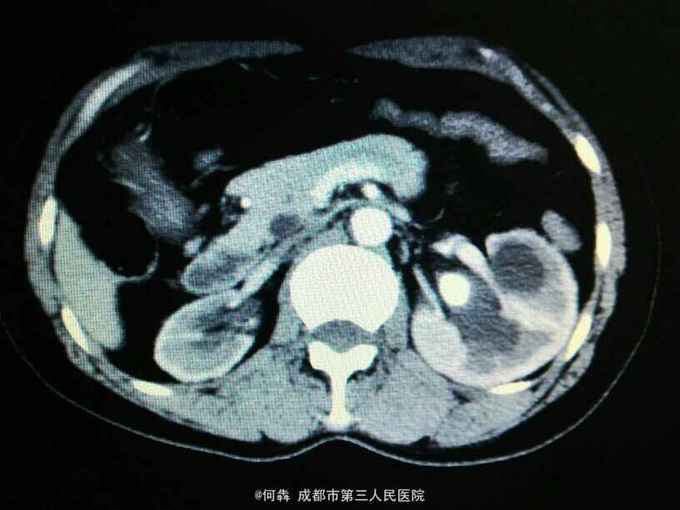

左肾区轻叩痛。尿常规:白细胞72个/ul。CT见图片。左侧GFR42.27,右侧GFR14.46。

左肾盂输尿管交界处结石 左肾重度积水,左肾结石,右肾萎缩,尿路感染。